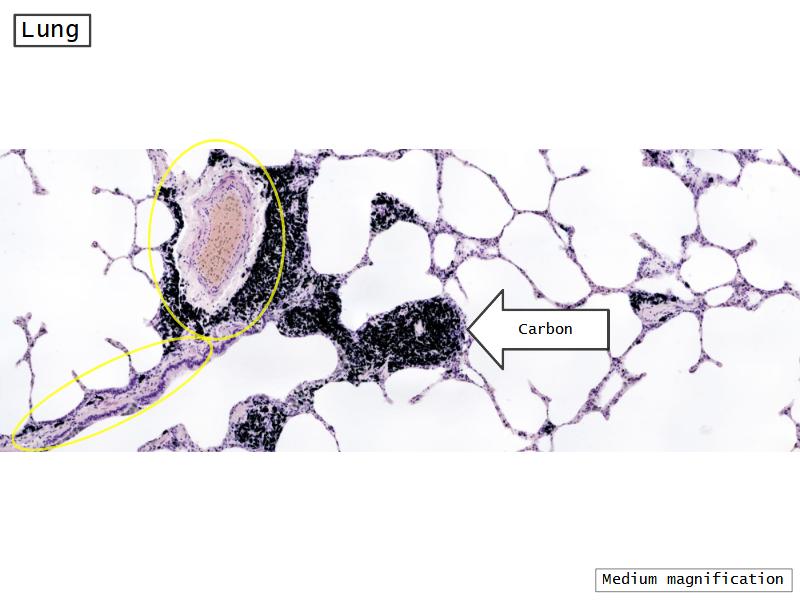

- Slide 72 & 74: Lung

- Alveoli

Lungs